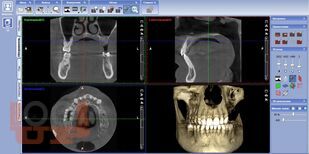

Учебное пособие содержит необходимую современную информацию, не отраженных в основной учебной литературе. Описаны основные методы лучевой диагностики, используемые в клинической практике врача стоматолога и челюстно-лицевого хирурга. Освещены основы лучевой диагностики стоматологических заболеваний, радиационной безопасности при их применении.

В нем, кроме теоретического материала, для контроля освоения знаний представлены тестовые задания и ситуационные задачи с эталонами ответов, а также авторские иллюстрационные материалы и их интерпретация.